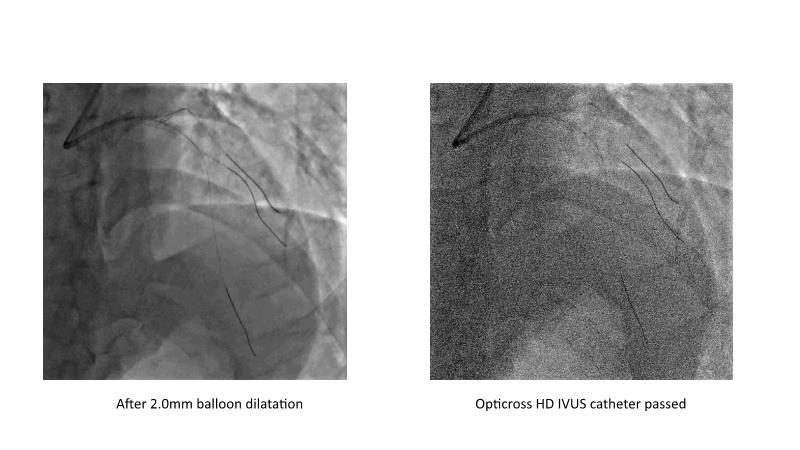

This session is recommended for you if you are seeking insights into the advantages of using IVUS imaging over visual assessment for better outcomes in left main bifurcation procedures. Discuss with experts the benefits of using RotaCUT in lesion preparation for left main bifurcation and explore the impact of high radial strength stents on the procedure's success.

• To understand why the use of IVUS imaging is different from seeing with experienced eyes to achieve improved left main bifurcation outcome

• To see advantages of RotaCUT as part of lesion preparation in left main bifurcation